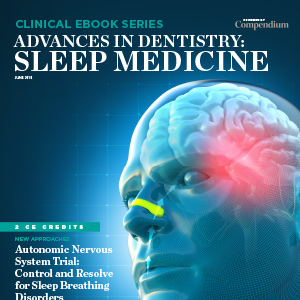

Advances in Dentistry: Sleep Medicine

Undiagnosed sleep apnea significantly impacts one's health and productivity, so oral healthcare practitioners are increasingly expanding their practices to help their patients with breathing-disturbed sleep. In this special eBook from Compendium, two perspectives on dental sleep medicine are present...